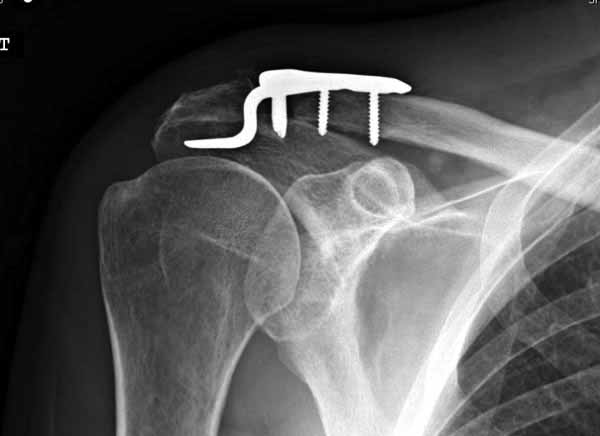

foto

2.JPG

12KB (12589 bytes)

|